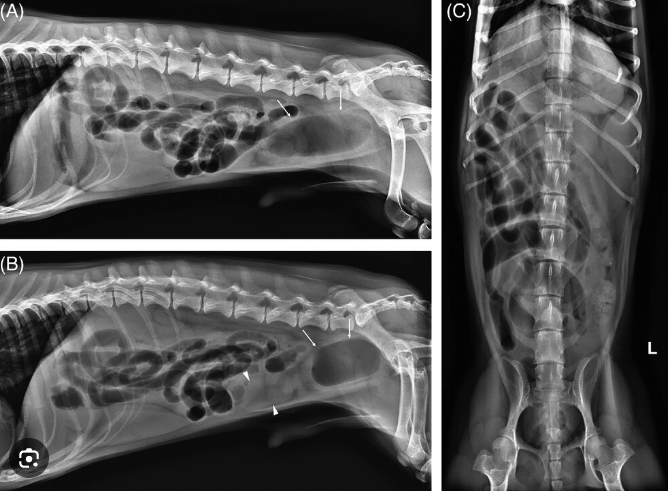

이번에 나온 논문은 공장이 꼬인 강아지에 대한 논문이다.

항상 그렇지만 'a dog' 를 가지고 논문을 쓰는것은 그만큼 희귀하다는것이나

오직 시야를 좁히지 않고 '이런것도 있을 수 있다' 라는 것을 상기하며 진단의 다양성을 확보하기 위해 기억해 두어야 한다.